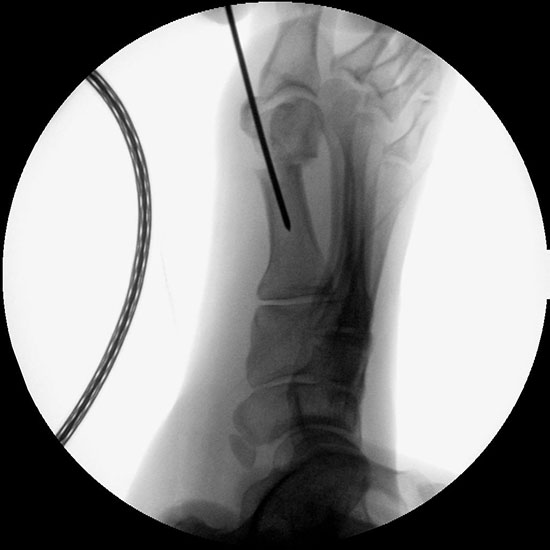

• Bildverstärker für intraoperative Kontrollaufnahmen.

• Bildverstärker.

• Lagerung des Beins auf einem gepolsterten Untergrund. Positionierung des Bildverstärkers im 90° Winkel zur Fußlängsachse (Abbildung 4).